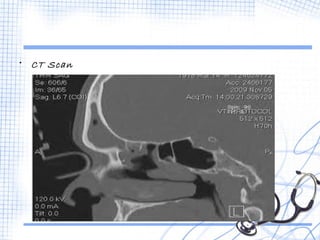

• CT Scan